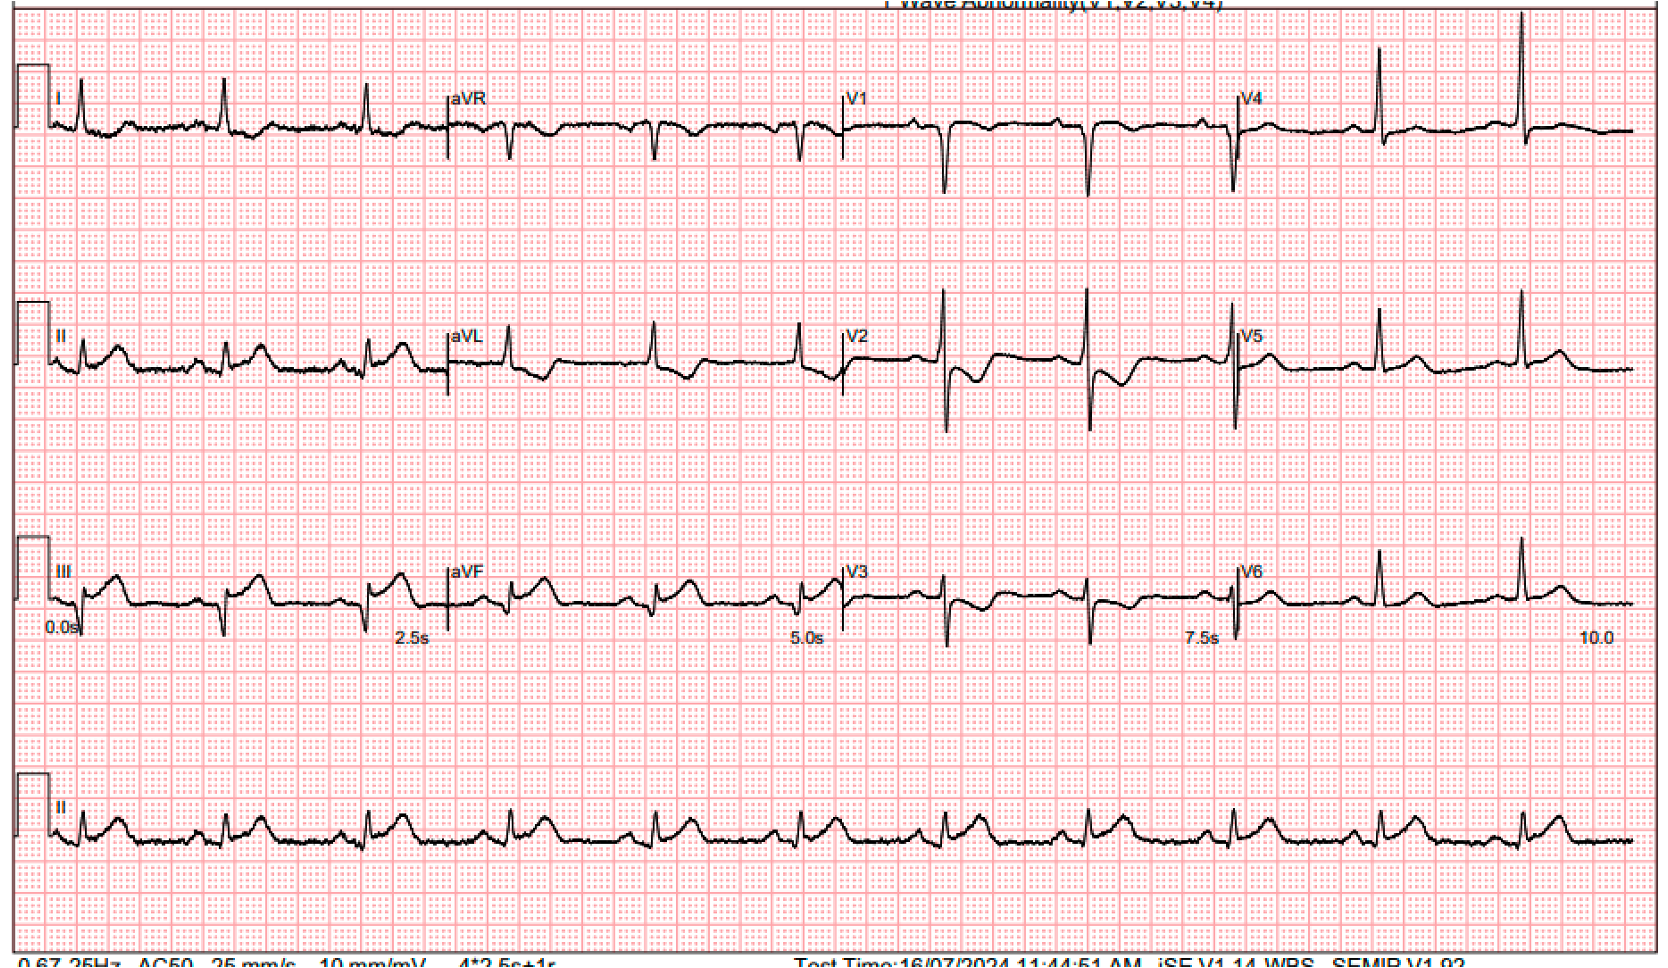

She presented with acute chest pain for 3 hours. In the emergency department, an ECG revealed sinus rhythm with inferior ST elevations. She was still in active chest pain. Physical exam was otherwise unremarkable.

She presented with acute chest pain for 3 hours. In the emergency department, an ECG revealed sinus rhythm with inferior ST elevations. She was still in active chest pain. Physical exam was otherwise unremarkable.

In the emergency department, an ECG revealed sinus rhythm with inferior ST elevations. A bedside echocardiogram indicated an impaired LVEF of 40%, with inferior hypokinesia. There was no pericardial effusion or signs of aortic dissection, and hemodynamics were stable. CXR showed clear lung fields. We proceeded with primary PCI.